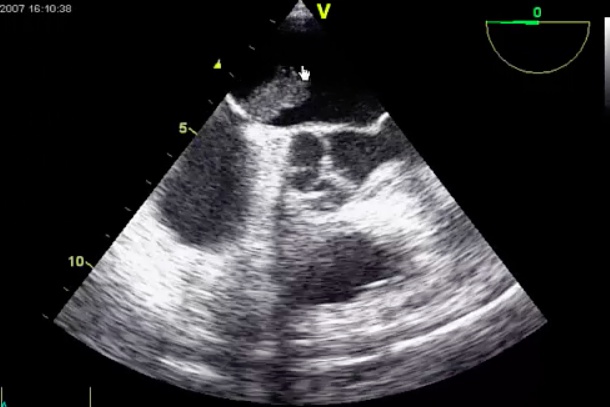

Myxoma

obstruct flow: ball in valve

pt die suddenly. Autopsy finds myxoma. Cause of death: MV obstruction